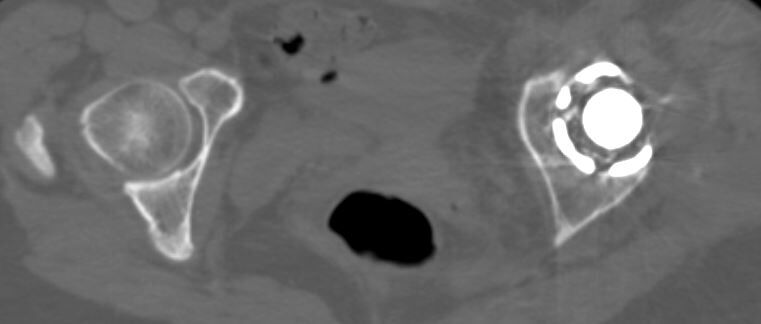

しかし、術前CTで寛骨臼の前方開角が45度、大腿骨頚部前捻角が40度でした...。大腿骨頚部前捻角はまだしも、寛骨臼前方開角は看過できません。

このままの角度でカップを設置すると前方脱臼する可能性があります。しかし、前方開角を減じるとカップ前方で腸腰筋との Irritationを併発して股関節痛を残す原因となりそうです。

かなり検討したのですが、結局カップの前方開角度は通常の症例と同様に20度に減捻して、腸腰筋の Irritationにはある程度目をつぶることしました。